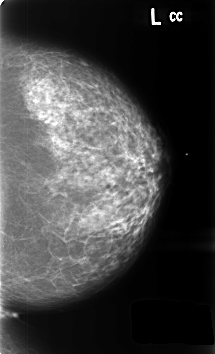

B_3459_1.LEFT_MLO

B_3459_1.LEFT_CC

LEFT_MLO LINES 4640 PIXELS_PER_LINE 2872 BITS_PER_PIXEL 12 RESOLUTION 50 NON_OVERLAY

LEFT_CC LINES 4592 PIXELS_PER_LINE 2784 BITS_PER_PIXEL 12 RESOLUTION 50 NON_OVERLAY